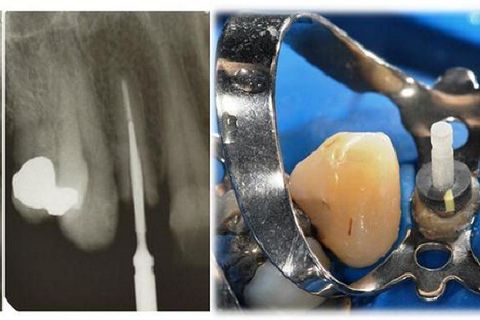

• Figura 2. Preparo do conduto radicular para pino Exacto n. 2 (Angelus) translúcido, utilizando broca so Sistema Exacto em baixa rotação. Observe a manutenção de aproximadamente 5,0mm de guta-percha no terço apical. Prova clínica do pino após isolamento absoluto.

• Figura 6. Manipulação do cimento de presa química Cement-Post (Angelus), seguida de inserção do cimento com lima, espalhando nas paredes do conduto radicular. Inserção do pino de fibra envolvido com cimento resinoso. Remoção dos excessos de cimento com micro-brush.